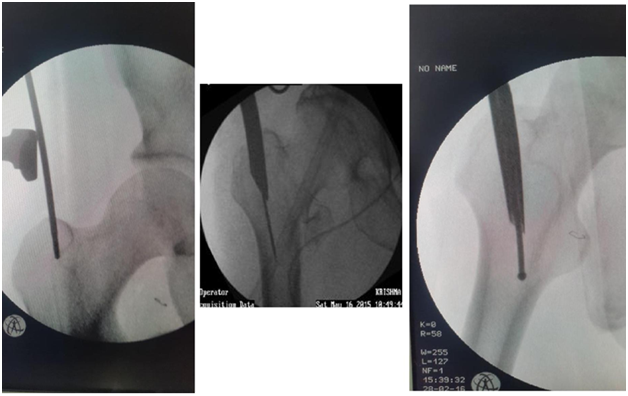

Indications (Figure 1)

1. Unstable IT fractures

1. Comminuted

2. Reverse oblique

3. Subtrochanteric extension

2. Associated shaft fracture

Figure 1 PFN in IT fractures.